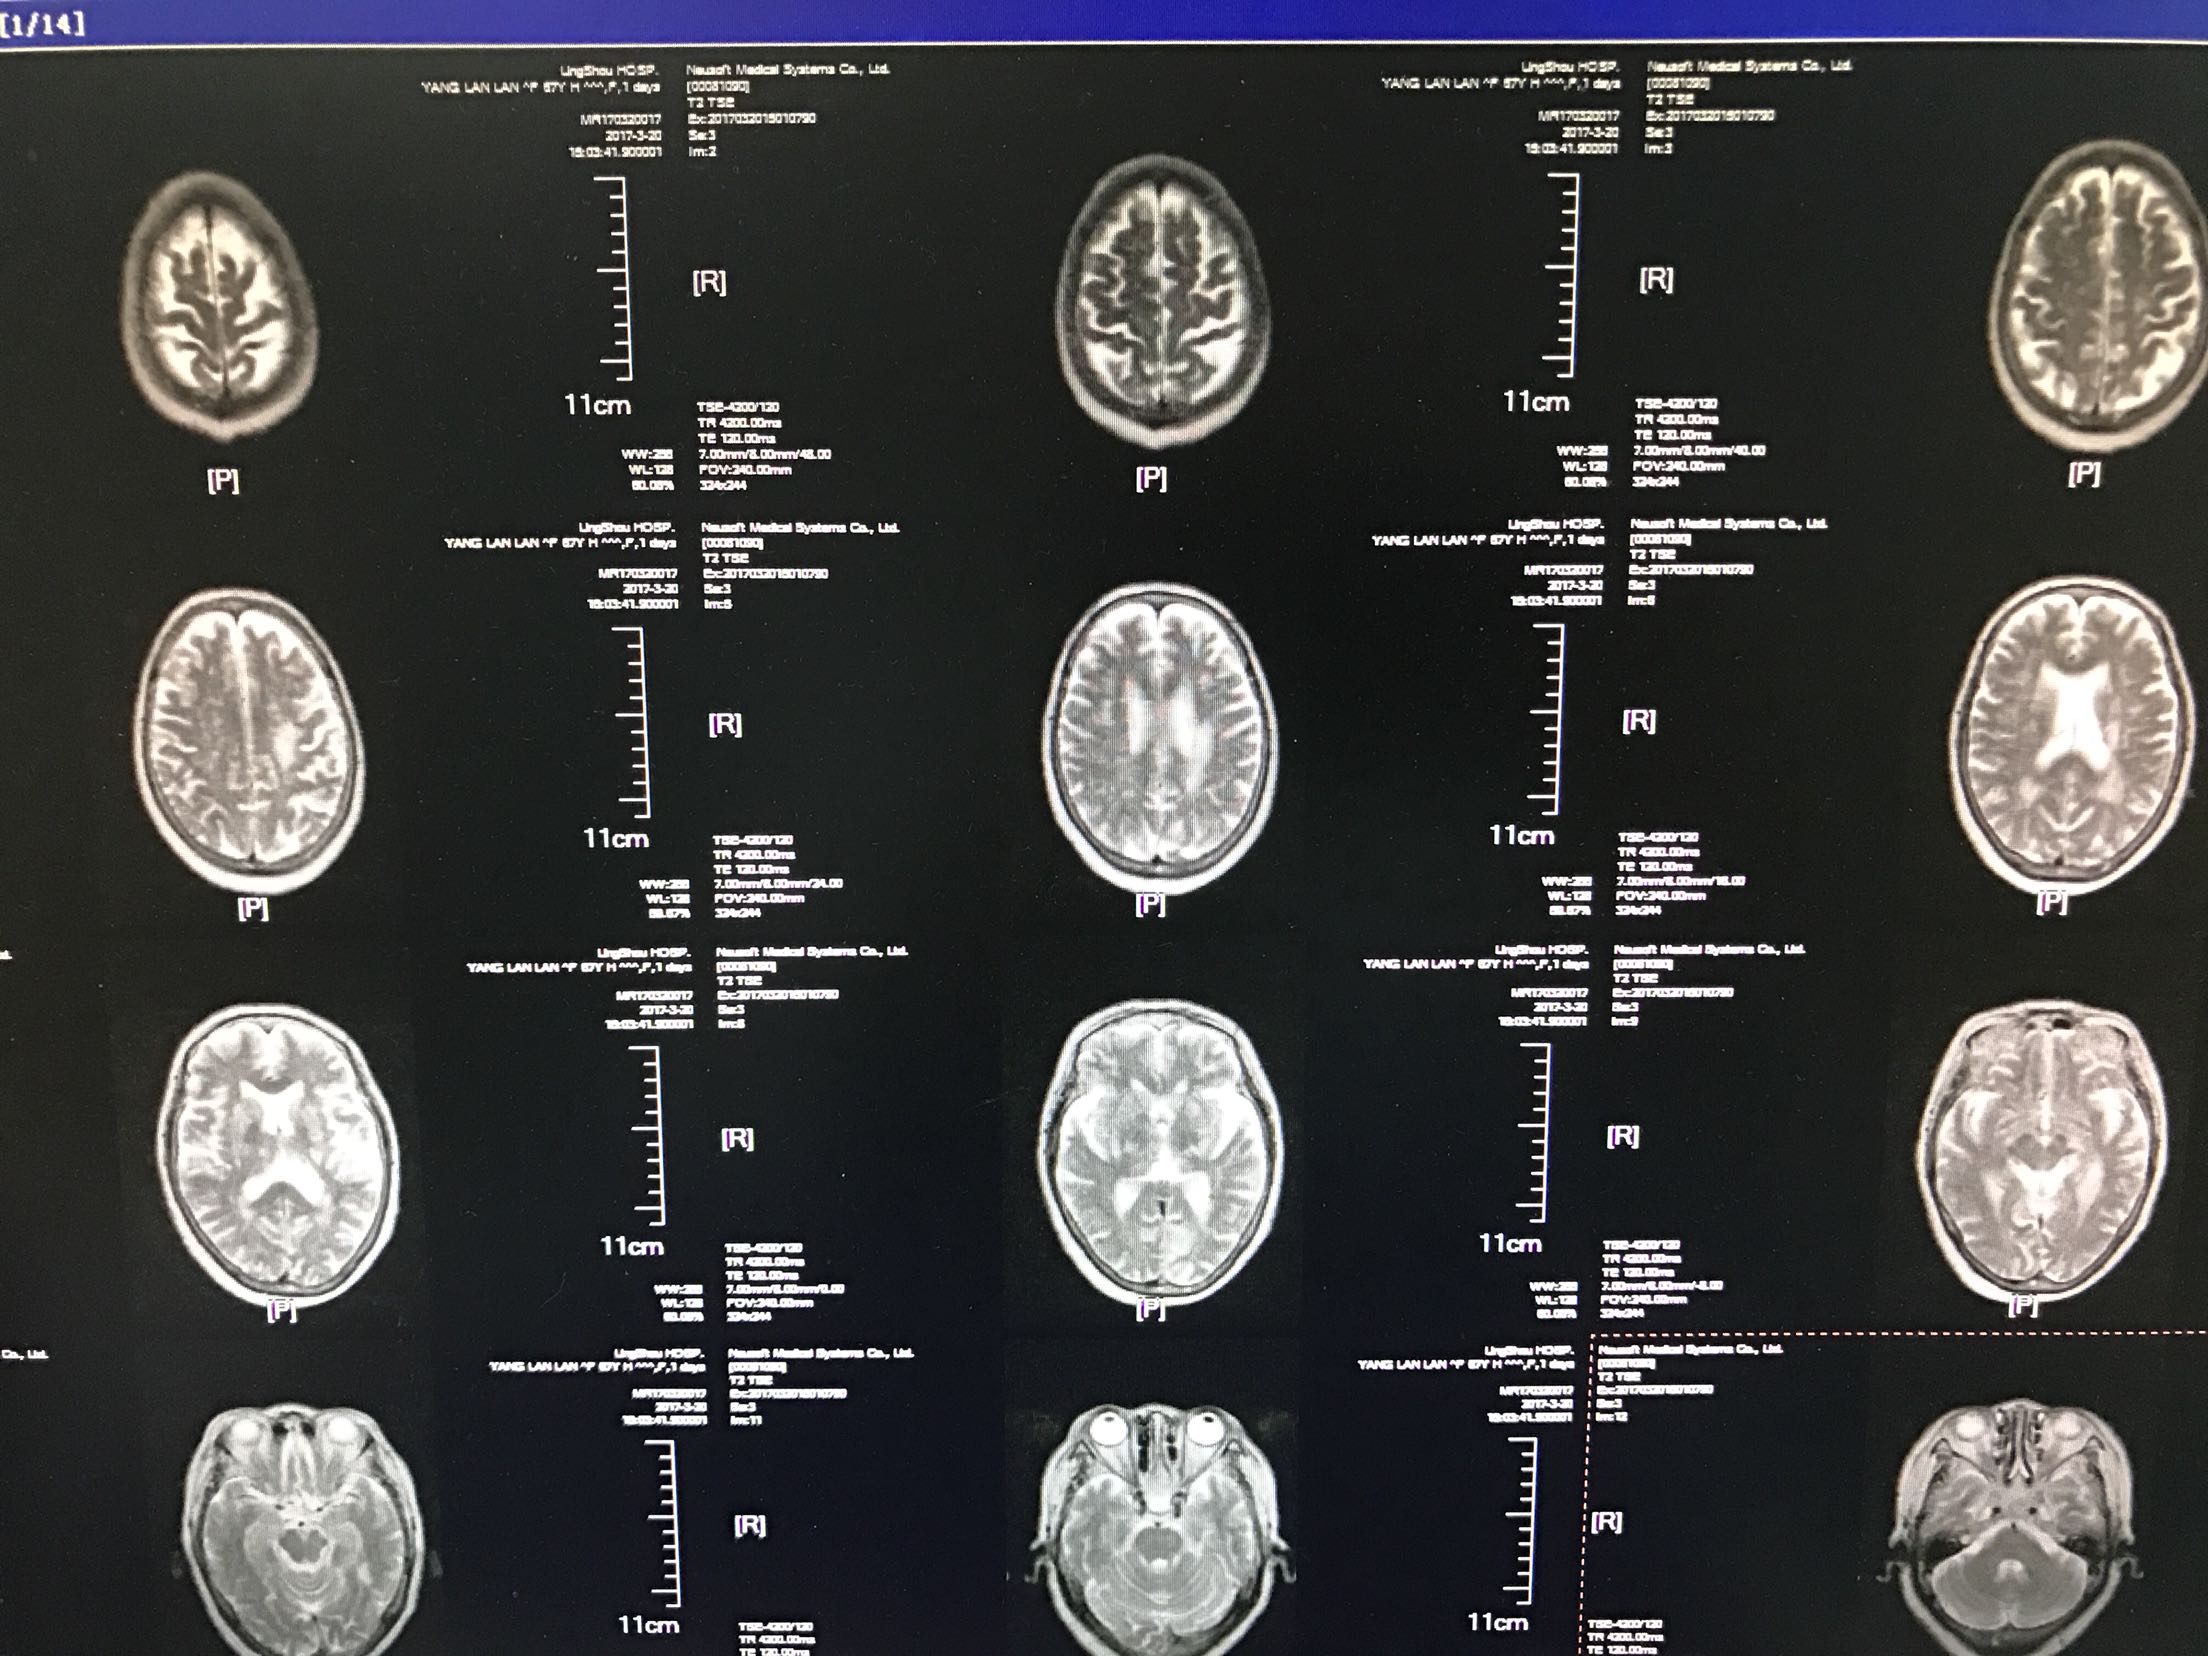

患者中年女性55岁,主因右侧肢体无力,言语不利1天入院,既往糖尿病病史5年,平素口服二甲双胍及格列吡嗪,未控制饮食,自诉血糖控制不佳,时高时低!脑出血病史4年,留有左侧肢体无力,生活尚能自理,患者缘无1天前,活动时突然出现右侧肢体无力,右上肢尚可抬起,持物不牢,右下肢不能负重,不能自行行走,同时出现言语不利,说话含糊不清,但无听理解障碍,查CT:双侧基底节,左丘脑腔梗及软化灶,测血糖18.3mmol/l,为进一步治疗收住院

体温36.9℃脉搏106次/分,呼吸20次/分,血压140/87mmhg,神情,言语欠流利,眼动充分,无水平性眼震,伸舌居中,颈无抵抗,双肺呼吸音清,未闻及干湿性啰音,心音低钝,心律规整,未闻及杂音,左侧肢体肌力2级,右侧肢体肌力4级,双巴氏征阳性,克氏征阴性,

1.脑梗死2.2型糖尿病3.脑出血后遗症期,给于抗凝,降血糖,抑制血小板聚集,稳定动脉板块等治疗